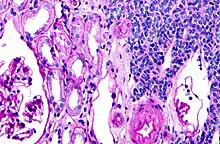

| Micrograph of a metanephric adenoma with structures reminiscent of those seen in papillary renal cell carcinoma. H&E stain. | |

Metanephric adenoma (MA) is a rare, benign tumour of the kidney, that can have a microscopic appearance similar to a nephroblastoma (Wilms tumours),[1] or a papillary renal cell carcinoma.

Metanephric adenoma is diagnosed histologically. The tumours can be located at upper pole, lower pole and mid-hilar region of the kidney; they are well circumscribed but unencapsulated, tan pink, with possible cystic and hemorrhagic foci. They show a uniform architecture of closely packed acinar or tubular structures of mature and bland appearance with scanty interposed stroma.[3][4][5][6][7] Cells are small with dark staining nuclei and inconspicuous nucleoli. Blastema is absent whereas calcospherites may be present. Glomeruloid figures are a striking finding, reminiscent of early fetal metenephric tissue. The lumen of the acini may contain otherwise epithelial infoldings or fibrillary material but it is quite often empty. Mitoses are conspicuously absent.[3][4][5][6][7] In the series reported by Jones et al. tumour cells were reactive for Leu7 in 3 cases of 5, to vimentine in 4 of 6, to cytocheratin in 2 of 6, to epithelial membrane antigen in 1 of 6 cases and muscle specific antigen in 1 of 6.[5] Olgac et al. found that intense and diffuse immunoreactivity for alpha-methylacyl-CoA racemase (AMACR) is useful in differentiating renal cell carcinoma from MA but a panel including AMACR, CK7 and CD57 is better in this differential diagnosis.[8] Differential diagnosis may be quite difficult indeed as exemplified by the three malignancies initially diagnosed as MA that later metastasized, in the report by Pins et al.[9]